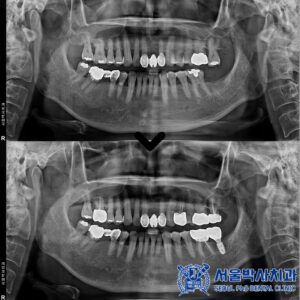

태평동치과 잇몸이 부었어요. 뼈이식을 포함한 어금니임플란트 사례

태평동치과 잇몸이 부었어요. 뼈이식을 포함한 어금니임플란트 사례 치아는 가능한 한 보존하는 것이 좋지만, 다음과 같은 경우에는 발치가 불가피할 수 있습니다. 먼저, 잇몸 뼈가 많이 녹아 치아를 지지할 수…